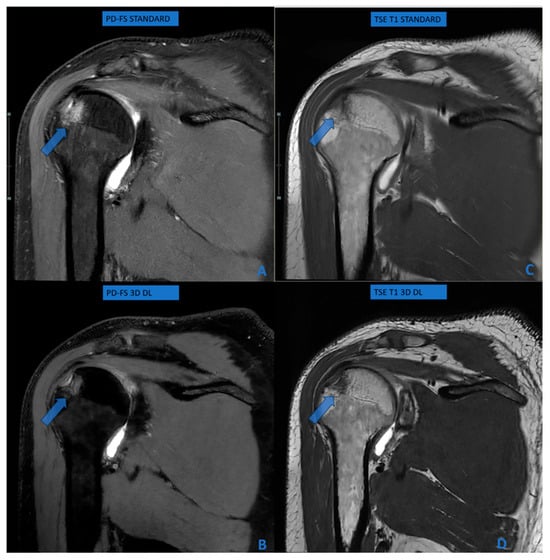

Accuracy of Deep Learning-Driven MR Arthrography of the Shoulder: Compressed 3D in Comparison to Standard FSE Sequences

by Gianluca Tripodi, Flavio Spoto, Giuseppe Ocello, Leonardo Monterubbiano, Paolo Avanzi and Giovanni Foti

Osteology 2026, 6(1), 4; https://doi.org/10.3390/osteology6010004 - 27 Feb 2026

Background/Objectives: Magnetic resonance arthrography is the reference standard for evaluating glenoid labral lesions. Deep learning (DL) reconstruction algorithms may accelerate 3D acquisitions while maintaining image quality. This study assesses the diagnostic accuracy of DL-based isotropic 3D MR imaging for detecting glenoid labral lesions. Methods: This prospective study included 128 consecutive patients (79 men, 49 women; mean age 38.4 years) undergoing shoulder MR arthrography between June 2023 and April 2025. DL-based 3D sequences (acquisition time: 3:26) were compared with conventional multiplanar TSE and PD-FS sequences (acquisition time: 24–28 min). Two independent radiologists assessed glenoid labral lesions, bone marrow edema, and rotator cuff abnormalities using a four-point Likert scale. Sensitivity, specificity, and interobserver agreement were calculated. Results: DL-based 3D sequences demonstrated 94.7–95.1% sensitivity and 100% specificity for glenoid labral lesions, with excellent interobserver agreement (κ = 0.812). The area under the ROC curve was 0.894. Combined 3D protocols (T1 + PD-FS) showed superior accuracy (97.8%) compared to single sequences (90.5%, p = 0.012). For bone marrow edema, sensitivity was 82.9% with 100% specificity. Rotator cuff evaluation achieved 75% sensitivity with 100% specificity. Conclusions: DL-based isotropic 3D sequences provide high diagnostic accuracy for glenoid labral pathology while reducing scan time by 75%. Combined T1 and PD-FS protocols optimize performance. These findings support selective implementation of DL-accelerated 3D protocols in shoulder MR arthrography, particularly for labral assessment, while acknowledging that conventional protocols may remain preferable in specific clinical scenarios. Full article

Figure 1